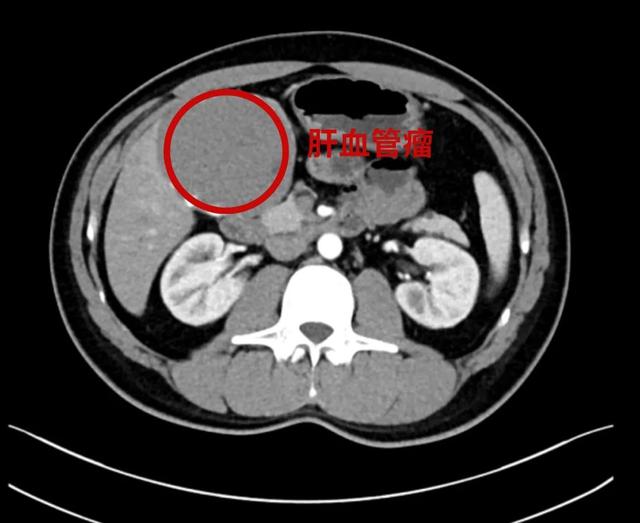

44歲的王先生8年前體檢發現肝血管瘤,無不適癥狀,定期復查。一月前患者自覺右上腹脹痛不適,且右肋緣下可觸及一包塊,立即到昆山市一醫院肝膽胰脾外科就診,查增強CT提示肝血管瘤,直徑達9cm,同時血管瘤內部合并局部出血。肝膽胰脾外科醫生根據王先生的相關檢查及臨床癥狀,建議行腹腔鏡下肝部分切除術,王先生表示同意。

增強CT可見肝血管瘤較大,且與膽囊緊密粘連